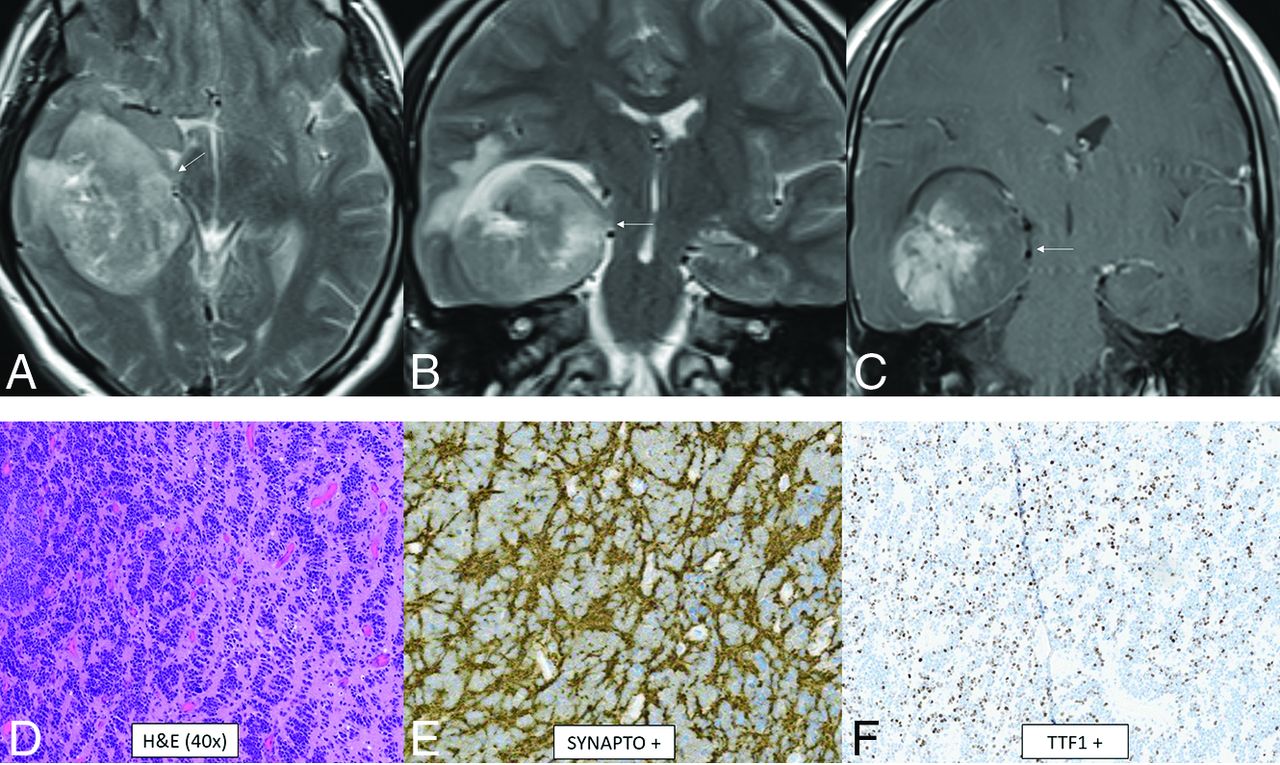

CNS Neuroblastoma, FOXR2-Activated

CNS neuroblastoma is a highly malignant embryonal tumor without an official WHO grade. These tumors have variable chromosomal rearrangements or mitochondrial DNA insertions converging on FOXR2, leading to overexpression.67,68 FOXR2 binds to and stabilizes MYC and MYCN proteins and therefore promotes MYC-related transcriptional activities, leading to increased cellular proliferation and tumorigenesis.67,68 Histology shows a small-cell tumor, embryonal architecture, a high proportion of neuropil, neurocytic cell, or ganglion cell differentiation, and, frequently, vascular pseudorosettes and nuclear palisades.67 OLIG2 and synaptophysin are positive.67 The median age is 4.5 years (range, 1.4–16 years) without a sex predilection.69 In the largest described series, tumors were large and supratentorial with invariable involvement of the deep white matter and frequent invasion of the cortex (80%) as well as a ventricular ependymal surface (64%).69 The frontal lobe was the most common location, though involvement of multiple regions was common. Typical tumors were multilobulated, solid, and cystic/necrotic, T2-hyperintense, enhancing, and diffusion-restricting (Fig 10). Calcification or hemorrhage was present in approximately 40% of tumors. Calvarial remodeling was present in nearly half of cases and occurred more frequently with larger tumors.

CNS neuroblastoma, FOXR2-activated. MR images show a large cortical and subcortical well-circumscribed expansile mass in the right temporal lobe involving the hippocampus (arrows) with T2-hyperintensity (A and B) and patchy enhancement (C). Histology shows a highly cellular infiltrating neuroepithelial neoplasm with a complex pattern, including an undifferentiated and extensive spongioblastoma pattern with brisk mitotic activity (D). On immunohistochemistry, the tumor shows divergent differentiation with expression of synaptophysin (E), OLIG2, and TTF1 (F). Whole-genome methylation profiling indicated a match to CNS neuroblastoma, FOXR2-activated.